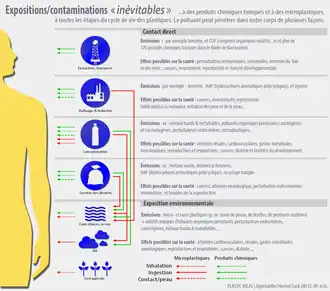

Leurs impacts (locaux et globaux, immédiats et/ou différés) ne sont étudiés que depuis le début des années 2000 et sont encore mal cernés. En termes de santé humaine et de santé environnementale et celles de nombreux animaux, avec les nanoplastiques, ils ont des effets indirects (en se dégradant ou via la contamination des océans) et possiblement des effets directs (on en trouve dans les plaques d'athéromes chez plus de la moitié des patients qui en ont, et ces derniers risques plus que ceux qui n'en ont pas de faire un AVC ou un infarctus).

Enjeux sanitaires

Les effets directs et indirects de l'ingestion de ces microplastiques sur la santé sont encore inconnus[5], cependant la libération spontanée de bisphénol A (perturbateur endocrinien) par certains plastiques suggère une part de responsabilité des microplastiques dans l'infertilité ainsi que certains troubles du développement grandissant chez la population. En raison de leur taille, les microplastiques sont plus biodisponibles. Ils sont par exemple ingérables par des détrivores ou des planctophages[18].

La principale préoccupation sanitaire pour l'homme a d'abord porté sur les colorants, additifs et molécules chimiques toxiques et cancérigènes ou mutagènes utilisés pour fabriquer nombre de ces plastiques ; on a ensuite aussi pensé puis montré que :

- les microplastiques sont aussi des « trojans » (ou « chevaux de Troie ») en tant que support et vecteur de nombreux toxiques (hydrocarbures, métaux lourds et métalloïdes, et même pesticides[57] et radionucléides[58] ; au moins deux études récentes[59] ont expérimentalement montré démontré que l'adsorption de radionucléides sur des microplastiques issus de « plastiques commerciaux » courants) et les biofilms qui recouvrent les microplastiques incluent potentiellement aussi des agents pathogènes[60] ;

- notre sang est fréquemment pollué par les micro- et nano- plastiques. Ainsi une étude italienne faite (2019-2020) publiée en 2024 dans The New England Journal of Medicine, a observé une présence de microplastiques dans plus de 50 % des plaques d'athérome de l'artère carotide prélevées 257 adultes opérés pour athérosclérose (dépôts de cholestérol et autres substances finissant par obstruer des vaisseaux sanguins, cause d'AVC et d'infarctus)[61]. Les analyses faites par « pyrolyse, chromatographie en phase gazeuse, spectrométrie de masse, analyse des isotopes stables et microscopie électronique » ont montré qu'il s'agit bien de microplastiques (polyéthylène, surtout /ou polychlorure de vinyle)[62].

Les auteurs ont conclu que « dans cette étude, les patients présentant une plaque de l'artère carotide dans laquelle des micro et nanoplastiques ont été détectés présentaient un risque (4 fois) plus élevé d'infarctus du myocarde, d'accident vasculaire cérébral ou de décès de toute cause à 34 mois de suivi » (par rapport à ceux chez qui les MNP n'ont pas été détecté)[61].

La seule présence de plastique ne prouve pas que les microplastiques sont la cause ou la seule cause de ces maladies, mais des niveaux élevés de molécules inflammatoires ont aussi été trouvés dans les plaques en contenant, suggérant un risque accru de crise cardiaque et d'AVC. D'autres études sont nécessaires pour mieux évaluer un éventuel degré de cause à effet[61] ;

- risque de malformations congénitales dont anomalies de distance anogénitale, micropénis ou non descente testiculaire[63], à la suite de l'exposition de femmes en âge de procréer ou du fœtus in utero (aux phtalates et aux métabolites du DEHP connus pour interférer avec le développement de l'appareil reproducteur masculin) ;

- un large éventail de troubles peuvent être induits par le BPA (ingrédient des plastique), dont - à faible dose - maladies cardiovasculaires, diabète de type 2 et anomalies des enzymes hépatiques, notamment. Ces effets sont démontrés, mais le BPA est par exemple encore utilisés dans le polyester, et donc présent dans les milliards de fibres synthétiques libérés dans l'environnement par les vêtements et tissus polyester ;

- problèmes thyroïdien et hypophysaires : le tétrabromobisphénol A (TBBPA), autre ingrédient dangereux des plastiques, est utilisé comme retardateur de flamme, notamment dans les microcircuits. Il perturbe l'équilibre des hormones thyroïdiennes, de la fonction hypophysaire et est source d'infertilité[64].